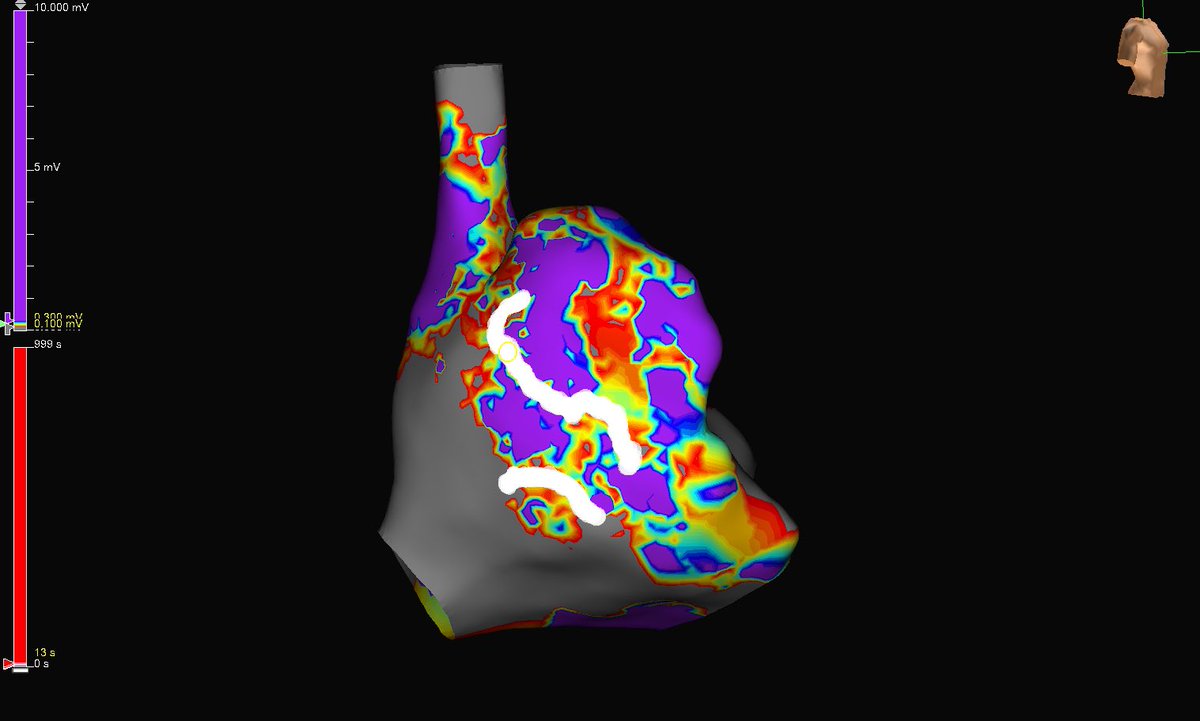

What could have been a lengthy homogenization of a massive inferior scar now becomes just a handful of burns in a small, but critical zone for VT. #mapmoreburnless

Hapa_EP's tweet image. What could have been a lengthy homogenization of a massive inferior scar now becomes just a handful of burns in a small, but critical zone for VT. #mapmoreburnless